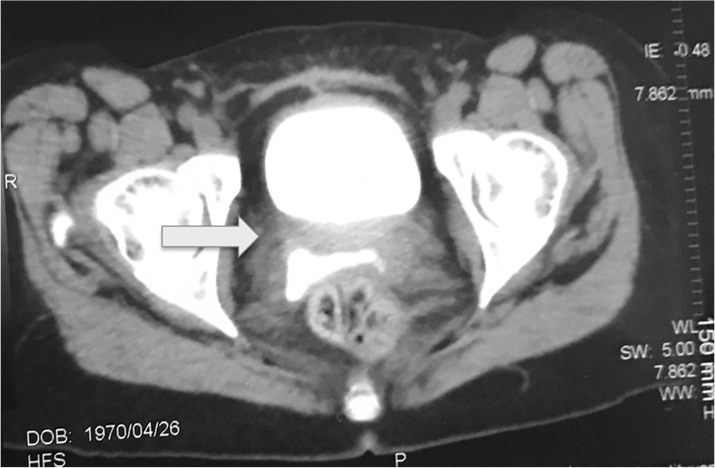

El cierre de la fístula se llevó a cabo con la técnica tradicional, además de colocar un reimplante ureteral izquierdo y un parche de epiplón. Al retirar la sonda ureteral izquierda (octava semana posquirúrgica) se observó, nuevamente, la salida de orina a través de la vagina, por lo que se efectuó el cierre de la fístula vesicovaginal recurrente, realizando un reimplante ureteral derecho y cierre del trayecto. La paciente egresó sin complicaciones y, posteriormente, se le retiró el catéter ureteral doble J derecho, además de la sonda Foley transuretral. Ante la persistencia de fuga de orina por la vagina se decidió realizar urotomografía, en la que se descartó la coexistencia de una fístula ureterovaginal, pero se observó una imagen hiperdensa, de 0.8 cm, en la zona postero-media de la vejiga, con paso del medio de contraste hacia la vagina (Figura 1).